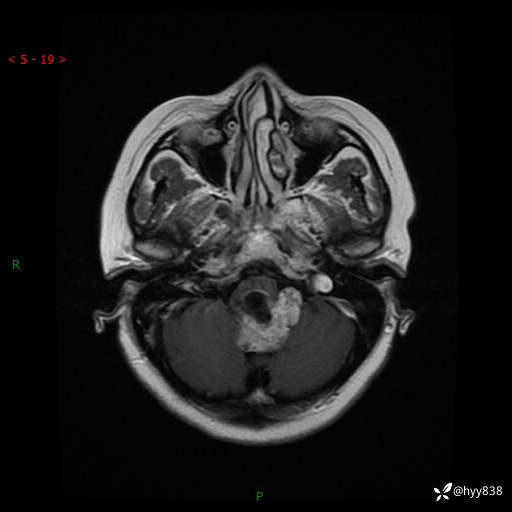

性别:女

年龄:47岁

简要病史:头晕1年余,间断恶心不伴呕吐

颅脑MRI平扫+DWI

轴内、轴外占位

病灶的影像特征

轴内或轴外肿瘤